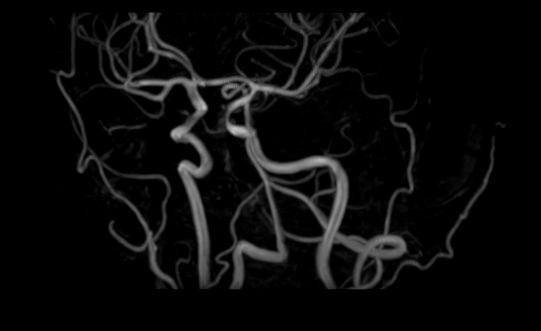

Стандартная МРТ головного мозга дает важную информацию о состоянии и структуре мозговой ткани для выявления большого числа заболеваний, в том числе опухолевых образований, демиелинизирующих заболеваний, воспалительных процессов головного мозга и мозговых оболочек. Стандартную МРТ головного мозга дополняет МР-ангиография, которая отображает состояние артериальной системы кровоснабжения головного мозга. МР-венография головного мозга позволяет детально изучить особенности анатомического и функциональной состояния венозного русла головного мозга.

Компьютерная программа обрабатывает данные, полученные при сканировании, и формирует объемные изображения как самого мозга, так и сосудистой системы в отдельности без прилегающих тканей. Обе методики применяются одновременно и взаимодополняют друг друга, давая полную диагностическую картину.